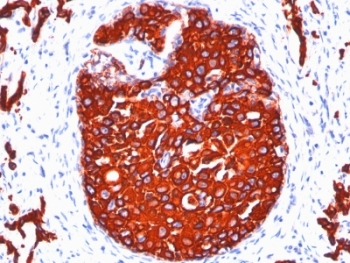

Twenty human keratins are resolved with two-dimensional gel electrophoresis into acidic (pI 6.0) subfamilies. This antibody cocktail recognizes acidic (Type I or LMW) and basic (Type II or HMW) cytokeratins, which include Keratins 1, 3, 4, 5, 6, 8, 10, 14, 15, 16, and 19. Many studies have shown the usefulness of keratins as markers in cancer research and tumor diagnosis. KRTL/KRTH is a broad spectrum anti pan-cytokeratin antibody cocktail, which differentiates epithelial tumors from non-epithelial tumors e.g. squamous vs. adenocarcinoma of the lung, liver carcinoma, breast cancer, and esophageal cancer. It has been used to characterize the source of various neoplasms and to study the distribution of cytokeratin containing cells in epithelia during normal development and during the development of epithelial neoplasms. This antibody stains cytokeratins present in normal and abnormal human tissues and has shown high sensitivity in the recognition of epithelial cells and carcinomas.